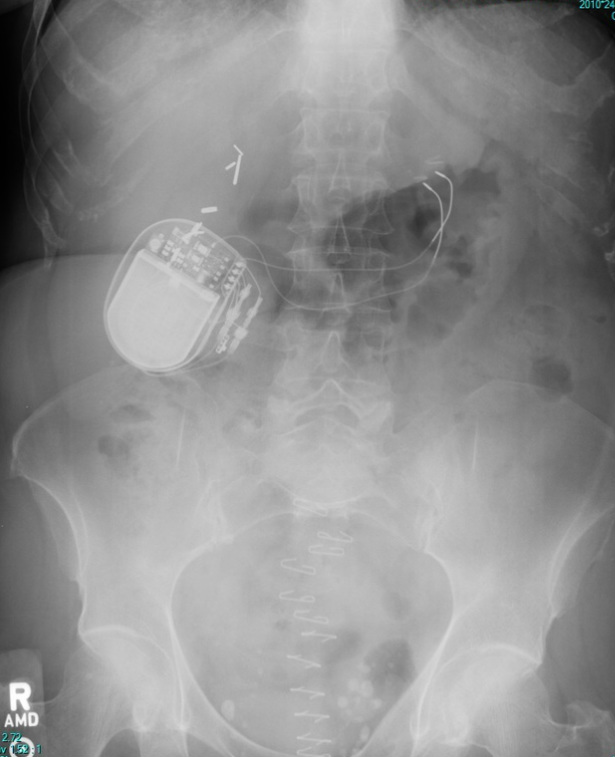

Surgically implanted devices are commonly seen on X-Ray. Being able to correctly identify is important. For the film above, identify the following:

The device is a gastric pacemaker.

Gastric pacemakers are used to treat gastric hypomobility, known as gastroparesis. Abnormally poor gastric motility interferes with normal digestion with food which in turn can alter blood sugar and other chemistry levels and overall patient nutrition. Nausea and vomiting may ensue, in additional to quickly feeling full when eating, weight loss, abdominal bloating and pain. Long term gastroparesis may result on malnutrition, dehydration, and, formation of bezoars - a hard mass-like conglomeration of undigested material which may lead to obstruction. Gastroparesis may be associated with diabetes or in some cases may be idiopathic but likely related to some insult to the vagus nerve.

Prior to having a gastric pacemaker implanted, attempts to improve gastric motility may be done using medications such as Raglan, erythromycin, or domperidone. There is some evidence that patient's may also benefit from alternative medicine, for instance acupuncture, acupressure, chiropractic, and biofeedback.